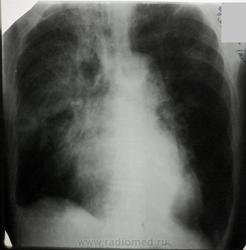

Негомогенное затенение вехней доли правого легкого полисегментарного объема гетерогенной интнесивности (от средней до высокой), с незначительным смещением трахеи вправо и тракцией правого корня кверху, с возможными полостями просветления в среднем легочном поле. Гиповентиляция правого легкого. Элевация купола диафрагмы справа, ограниченный гидроторакс в наружном реберно-диафрагмальном синусе справа и пристеночно (малое количество). Труба в трахее (интубация, ИВЛ). Слева - фокусные затенения верхней доли неправильной формы с неровным контуром. Кардиодилятация. Атеросклероз аорты.

Также "мерещится" большое круглое образование в проекции верхней доли справа, возможно, и осумкованный гидроторакс.

Диффдиагностика: ФКТ, рак правого легкого, правосторонняя деструктивная пневмония, ТЭЛА, инфаркт-пневмония. УХ, намешал! Разобраться бы.